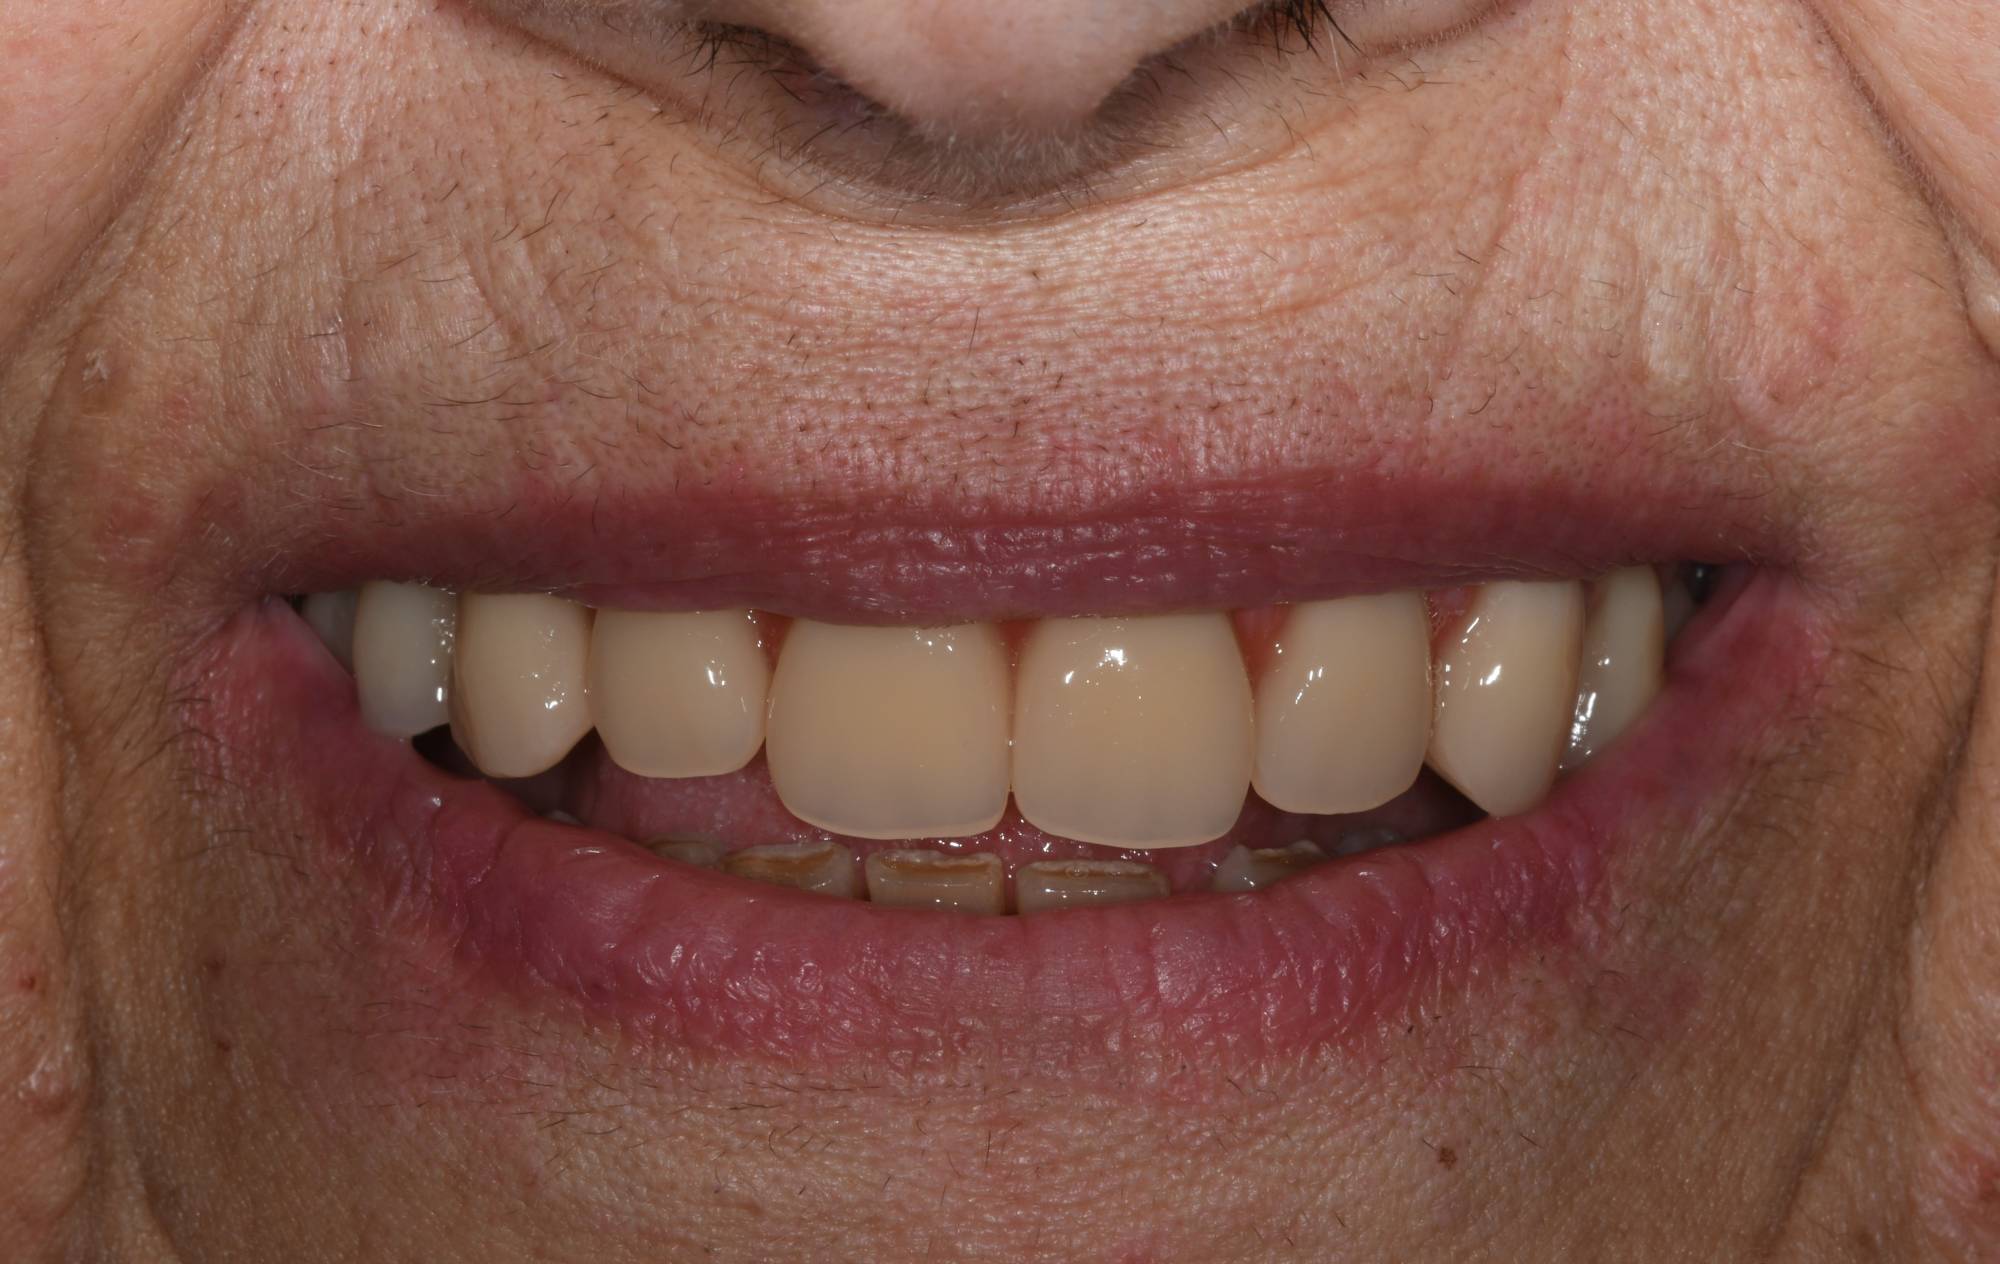

Puoi vedere le radiografie delle due barre avvitate nelle successive due foto. Sopra queste barre viene quindi avvitata l’ampia struttura metallica (che chiamiamo “secondaria”), che porta i denti artificiali di tutta l’arcata. E così, la signora si è ritrovata tutti denti fissi con cui può ridere, masticare e tornare ad una vita finalmente normale. Adesso confronta l’ultima foto con la prima e capirai come l’implantologia può cambiarti la vita in meglio. Questo è ciò a cui miriamo ogni giorno nello Studio dentistico del dott. Fabio Ballestrasse a Besana Brianza e se sei di Barzanò adesso sai a chi rivolgerti.